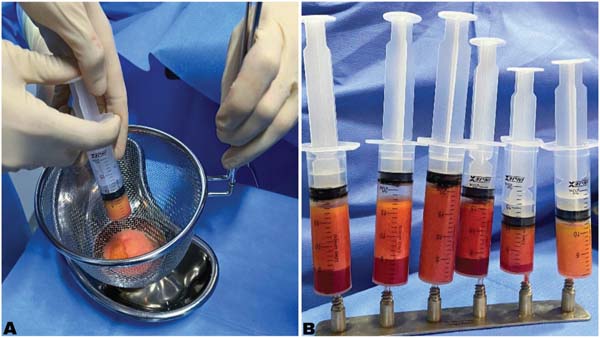

A coleta do tecido adiposo foi feita da região abdominal por incisão periumbilical precedida de anestesia local com lido-caína a 2%. A gordura foi colhida com cânula de 3 mm de diâmetro e 200 mm de comprimento e seringas de 20 mL, após infiltração do subcutânea com solução salina a 0,9% com adrenalina diluída na proporção de 1:500 mil. Em seguida, o tecido adiposo foi tratado conforme o grupo designado.

No grupo da filtração ele foi passado em uma peneira de aço inox de 16 cm e no grupo da decantação foi decantado em seringas mantidas verticalmente por 20 minutos, permitindo a separacao por gravidade de seus elementos so lidos (gordura) e líquidos ((óleo, solucao de soro, solucao salina). Apos este processo, o soro e o o leo separados da gordura foram descartados, sobrando apenas a gordura pronta para ser transplantada.

A gordura filtrada ou decantada foi transferida para seringas de 3 mL ou 10 mL com uso de transferidores de inox de duas vias. Ela foi então infiltrada na mama por uma pequena incisão com ca nulas simples de um furo (2 mm de dia metro e 200 mm de comprimento), estabelecendo tiú neis que permitam a retroinjecao fracionada no subcutaneo das áreas a serem corrigidas. ►Fig. 4.